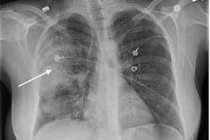

(khoahocdoisong.vn) - Các bệnh lý viêm nhiễm ở phổi thường do các tác nhân gây bệnh xâm nhập qua niêm mạc của đường hô hấp khi người bệnh hít phải các tác nhân này. Tuy nhiên, một “cửa ngõ” có thể là đường vào của nhiều loại vi khuẩn gây viêm phổi mà ít người để ý đó là da.